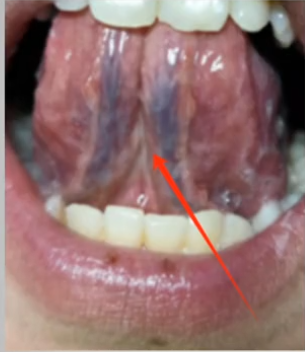

大家可以看看自己的舌头,要是舌下那两条青筋又粗又紫,那可得注意了——这就是体内淤血重的明明白白的信号!有这种情况的人,平时多半会觉得身上一阵一阵